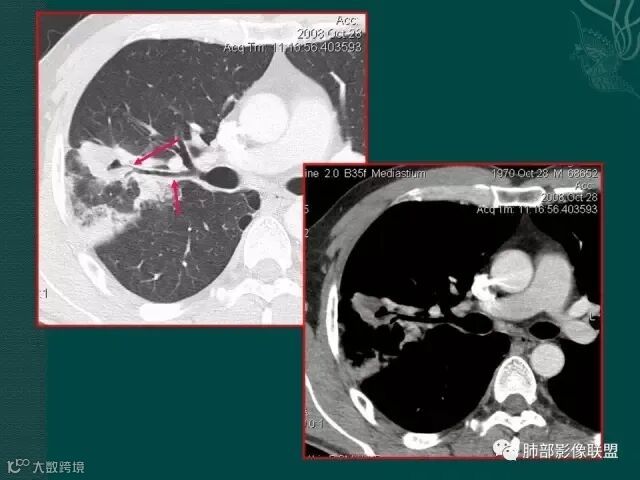

大片液化坏死,内多发空泡,初学者可能感觉是感染,但红箭头所指洞壁虽然不很厚,但仍可见到边界不清的低密度区,黄箭头所指病变侵犯胸膜。

病史似乎是炎性;空洞型病变,靠近纵隔的时候,一定要看对纵隔是否有侵蚀,这是相当重要的。

红箭头所指是右上肺静脉,起始部是完好的,上一层被病变完全包埋,管腔变窄,管壁形态不规则,并侵犯相邻纵隔。

肺癌靠近纵隔时,对纵隔的侵犯,对诊断有重要诊断价值,炎症的话很少会侵犯血管。